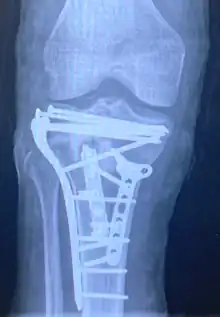

Treatment

Pain may be managed with NSAIDs, opioids, and splinting.[1][2] In those who are otherwise healthy, treatment is generally by surgery.[1] Occasionally, if the bones are well aligned and the ligaments of the knee are intact, people may be treated without surgery.[2] The surgery usually involves reducing the fractured fragments of the tibia plateau to their anatomical position and fixing them in place with screws only or fixed angle anatomical plates ensuring absolute stability. Implant selection is based on the type of injury. Generally, simple or incomplete fractures (Schatzker type 1) of the plateau are compressed with 6.5mm partially threaded cancellous screws. Complex type fractures will require a plate for enhanced stability. As the tibia condyles articulate with the femur (thigh bone) to form knee joint, any incongruity in the articular surface is unacceptable as it leads to early arthritis. Prolonged immobilization of the knee joint is also not recommended which result in stiffness of the joint and difficult recovery.